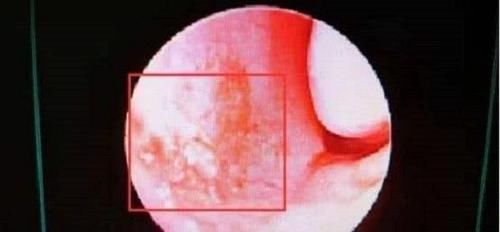

乐乐妈妈就是因为孩子流的鼻血特别多,还让孩子头仰起来,这样血就很容易进入血管和肺,致使孩子失去了生命。对于孩子来说,流鼻血的原因有很多,下面来具体说说这几种原因。